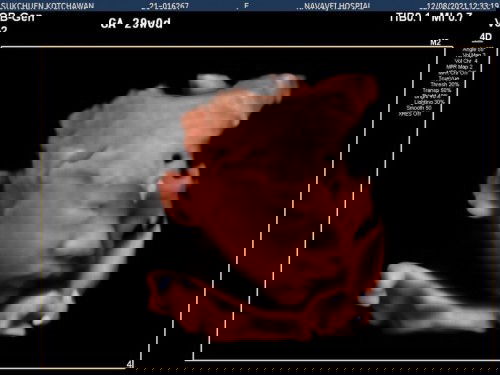

ตอนนี้ตั้งครรภ์ได้36สัปดาห์5วันแล้วค่ะ 🎉 นี้เป็นท้องแรกถือเป็นประสบการณ์ใหม่ในชีวิตของผู้หญิงคนนึง ตอนรู้ว่าท้องไตรมาสแรกเหม็นอาหารและกินข้าวไม่ค่อยได้ และของโปรดที่ชอบอยากส้มตำก็กินไม่ได้ 🤣อ้วกหนักมาก จนน้ำหนักลด 😭ทำให้เป็นห่วงเจ้าตัวเล็กในท้องมาก เป็นช่วงที่ศึกษาหาข้อมูลเยอะมาก พอเข้าไตรมาสที่สองอาการแพ้ท้องก็หายไป เริ่มร่าเริง มีความสุขในการตั้งครรภ์และการกิน ส่วนตอนนี้เข้าไตรมาสที่3เรียบร้อยค่ะ อาการตอนนี้ทำอะไรจะเหนื่อยง่าย และเข้าห้องน้ำบ่อยมาก😅ลางานอยู่บ้านเตรียมคลอดแล้วค่ะ✌️✌️✌️ ฉีดบาททะยักครบ3เข็มเรียบร้อย ส่วนวัคซีนโควิด💉ตอนแรกก็ว่าจะฉีดหลังคลอด แต่ที่ทำงานอยากให้ฉีดมาก เลยหาข้อมูลกับแฟนจนตัดสินใจฉีดไฟเซอร์ค่ะ เพิ่งฉีดเข็ม2วันที่4ต.ค ไป เข็มแรกมีอาการแค่ง่วงนอน ส่วนเข็ม2แขนข้างที่ฉีดมีอาการปวดเล็กน้อย ลูกยังดิ้นปกติดีค่ะ ส่วนใหญ่จะชอบดิ้นตอนกลางคืน😊น้ำหนักจาก45ตอนนี้62เป็นที่เรียบร้อย ส่วนเพศลูก เป็นผู้ชายคร้า 👶🏻 🌈กำหนดคลอด28ตุลาคมค่ะ #เลยอยากถามแม่ๆว่าส่วนใหญ่จะคลอดกันตอนกี่สัปดาห์ค่ะ ตอนนี้ตื่นเต้นและอยากแตกมากเลยค่ะ ใครมีประสบการณ์อยากแชร์ให้กันฟังได้เลยนะค่ะ 😍 ขอเป็นกำลังใจให้แม่ๆที่กำลังตั้งครรภ์ทุกคนนะค่ะ😘สู้ๆๆ